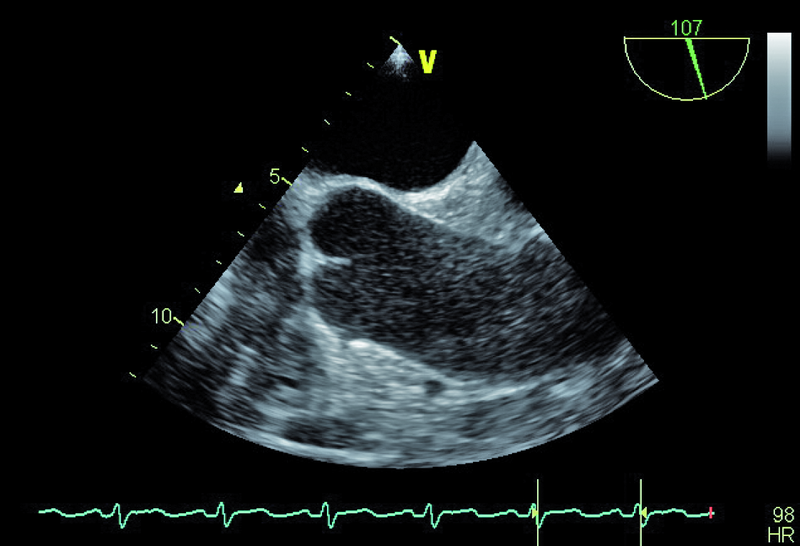

Pacjent, lat 60, z wywiadem nadciśnienia tętniczego, wieloletni palacz, został przyjęty do kliniki w celu oceny układu krążenia po przebytym rok wcześniej udarze mózgu. W przebiegu udaru obserwowano afazję ruchową, niedowład centralny nerwu VII, niedowład prawej kończyny górnej. Chory był intensywnie rehabilitowany, co przyczyniło się do stopniowego ustąpienia zaburzeń mowy oraz istotnej poprawy ruchomości prawej kończyny górnej. W tomografii komputerowej stwierdzono obszar hipodensyjny na pograniczu płata ciemieniowego i potylicznego lewej półkuli mózgu. Spektralne badanie doplerowskie tętnic szyjnych i kręgowych nie wykazało istotnych hemodynamicznie zaburzeń przepływu. Opiekujący się pacjentem neurolodzy podejrzewali, że przyczyną udaru mógł być przetrwały otwór owalny (patent foramen ovale, PFO). W wykonanych w klinice badaniach echokardiograficznych – przezklatkowym i przezprzełykowym – przegroda międzyprzedsionkowa była szczelna. Jama lewej komory była niepowiększona, a grubość mięśnia graniczna. Zwracało uwagę nieznaczne upośledzenie kurczliwości mięśnia komory (EF=50%) oraz poszerzenie aorty do 42 mm.

Wiek pacjenta, palenie tytoniu oraz chwiejne nadciśnienie tętnicze nakazują wykluczyć a priori tzw. kryptogenny udar mózgu. Przegroda międzyprzedsionkowa u chorego była szczelna, choć w badaniu przezprzełykowym (TOE) opisano śladowy kanał przetrwałego otworu owalnego (PFO), bez przechodzenia kontrastu ze strony prawej na lewą. Badanie przezprzełykowe pozwoliło także wykluczyć skrzeplinę w jamach serca (ryc. 1 – uszko lewego przedsionka) oraz istotne zmiany organiczne zastawki aortalnej (ryc. 2, 3). Prawdopodobną przyczyną udaru były nasilone zmiany miażdżycowe w łuku aorty z towarzyszącymi owrzodzeniami ściany naczynia (ryc. 4, 5). Warto zaznaczyć, że zmiany będące zgrubieniem błony wewnętrznej bywają dynamiczne i nie można wykluczyć powstawania ruchomych składowych (skrzeplin) na dużych elementach owrzodzenia. W diagnostyce miażdżycowego uszkodzenia aorty metodą z wyboru jest badanie przezprzełykowe, pozwalające zidentyfikować dzięki wysokiej rozdzielczości obrazu drobne, nawet kilkumilimetrowe owrzodzenia. Warto zaznaczyć, że badanie przezklatkowe nie dostarcza tak wyraźnego i jednoznacznego obrazu (ryc. 6). Korzyść z badania echokardiograficznego jest bez wątpienia większa niż z badania TK czy MR, ze względu na możliwość oceny ruchomości blaszek w czasie rzeczywistym. W rutynowej ocenie zwraca się uwagę na grubość blaszki miażdżycowej, obecność owrzodzeń, zwapnień oraz nałożonych ruchomych ech odpowiadających skrzeplinom – stanowiących tzw. potencjał zatorowy blaszki. Uważa się, że średnica blaszki przekraczająca 4 mm ma większy potencjał zatorowy niż owrzodzenie płytkie (w przedstawionym przypadku średnica blaszki wynosiła 7 mm). Dowiedziono ponadto, że w przypadku blaszek nieuwapnionych – jak w opisanej sytuacji – ryzyko zatoru jest większe niż w przypadku blaszek uwapnionych. Leczenie antykoagulacyjne w takim wypadku jest uzasadnione. Konieczne jest także włączenie dużej dawki statyn mimo braku zmian miażdżycowych w tętnicach wieńcowych (wykonano koronarografię). Ocena układu krążenia u pacjenta po przebytym incydencie zatorowym do OUN powinna być kompleksowa i powinna uwzględniać wszystkie możliwe nieprawidłowości.